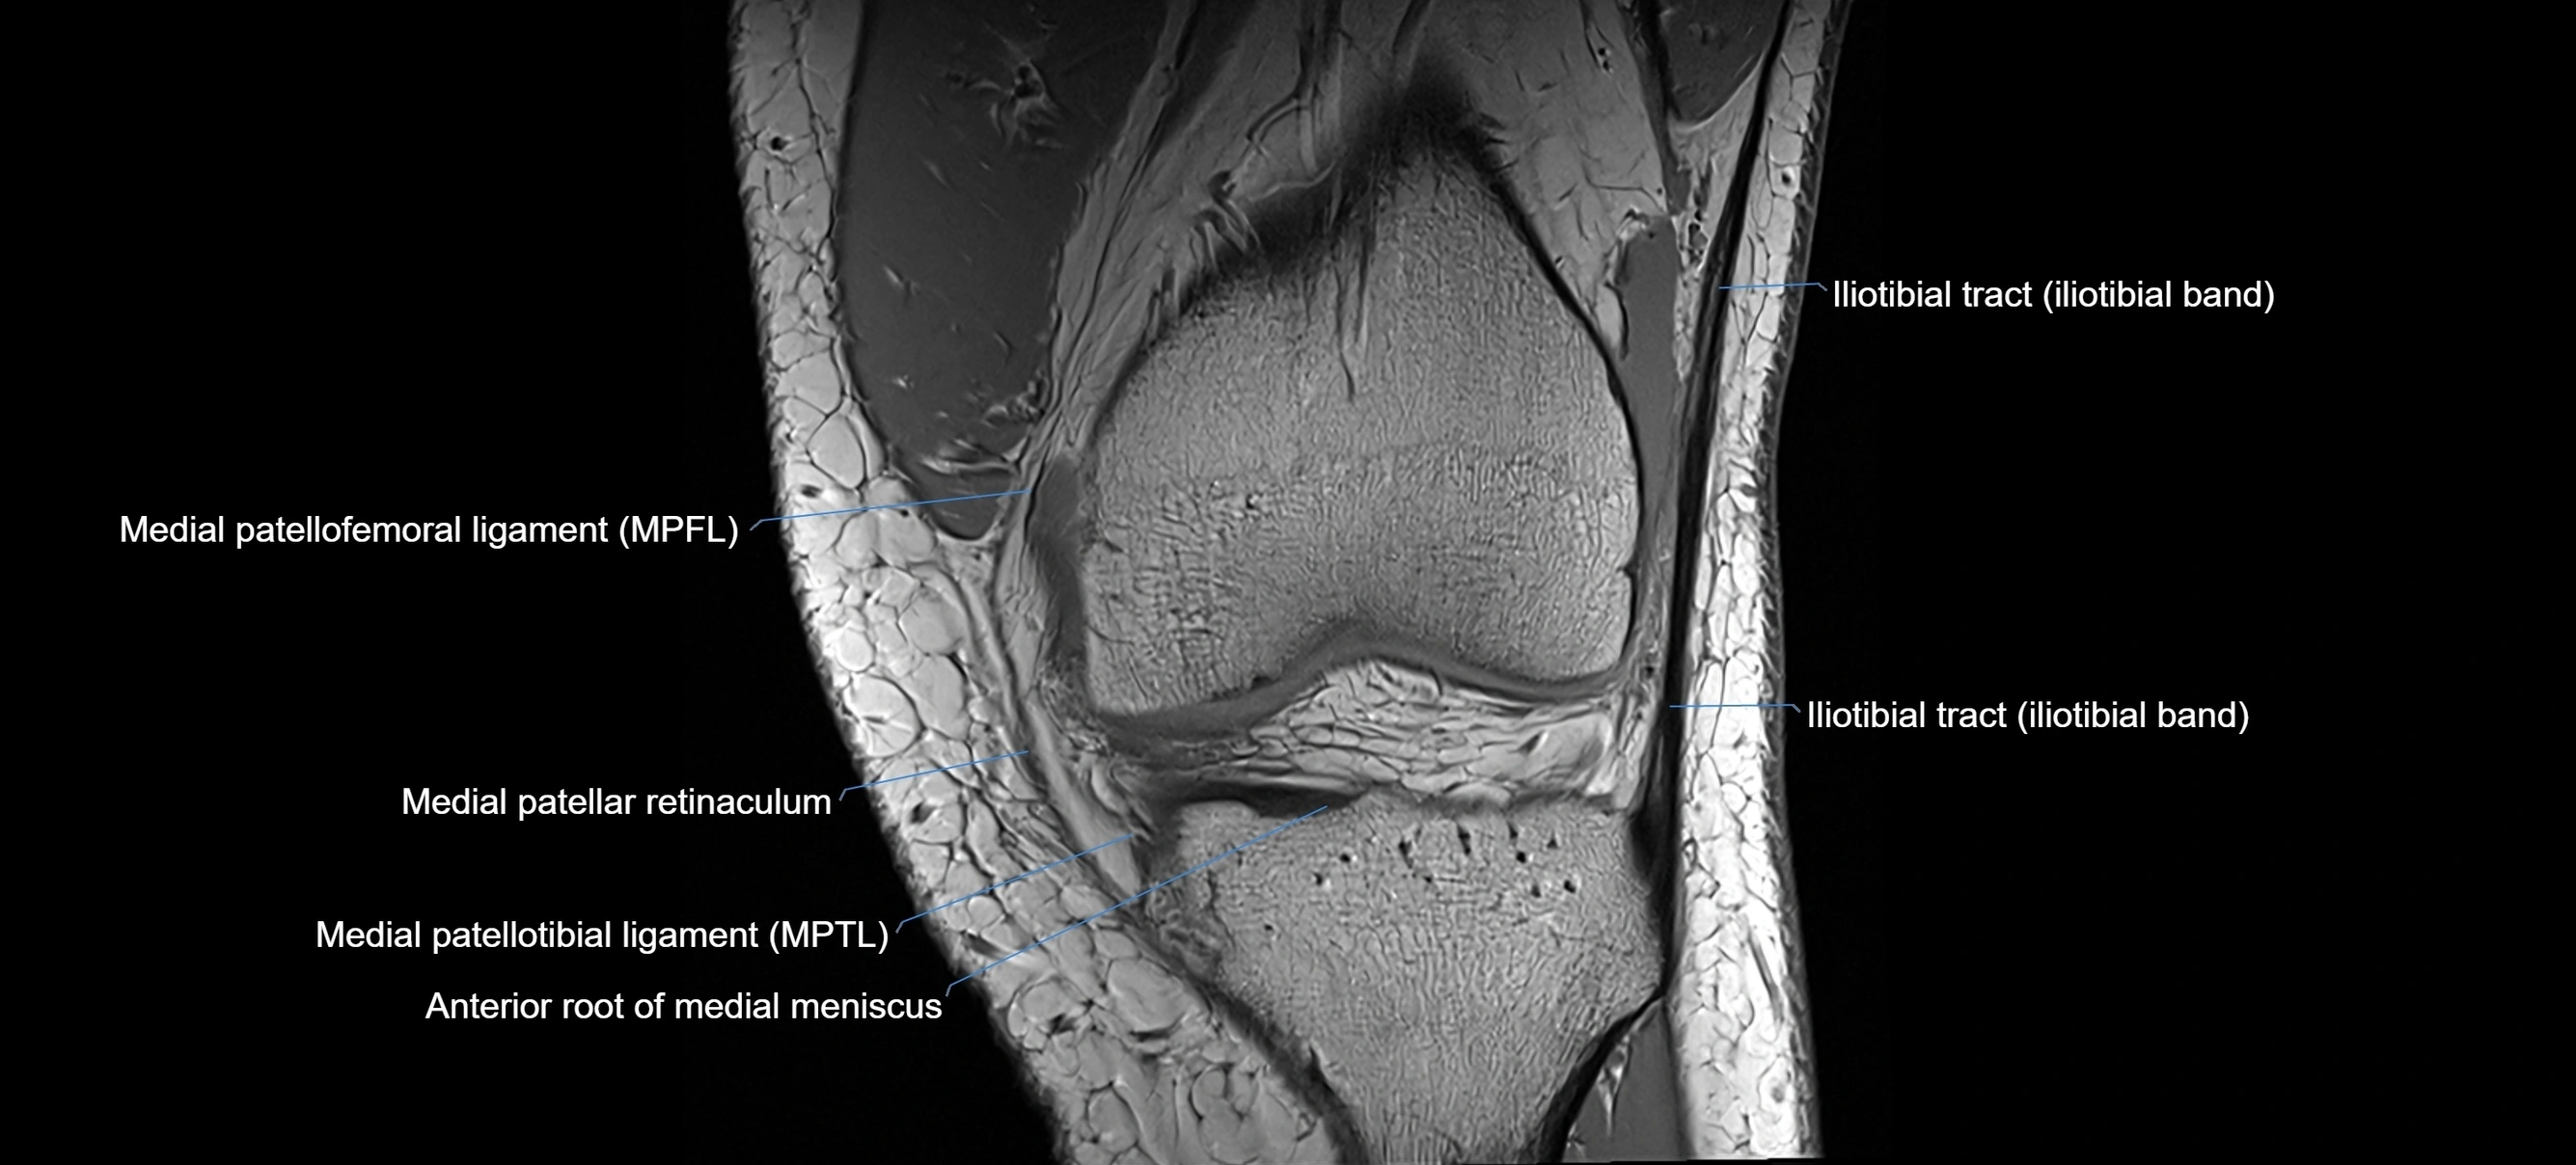

MRI images

image

MRI Appearance

T1-weighted images:

• Normal ACL appears as a low-signal band-like structure crossing the intercondylar notch

• Surrounded by intermediate signal synovial fluid and fat planes

T2-weighted images:

• Normal ACL remains low signal

• Partial or complete tears appear as discontinuity, increased signal, or fiber laxity